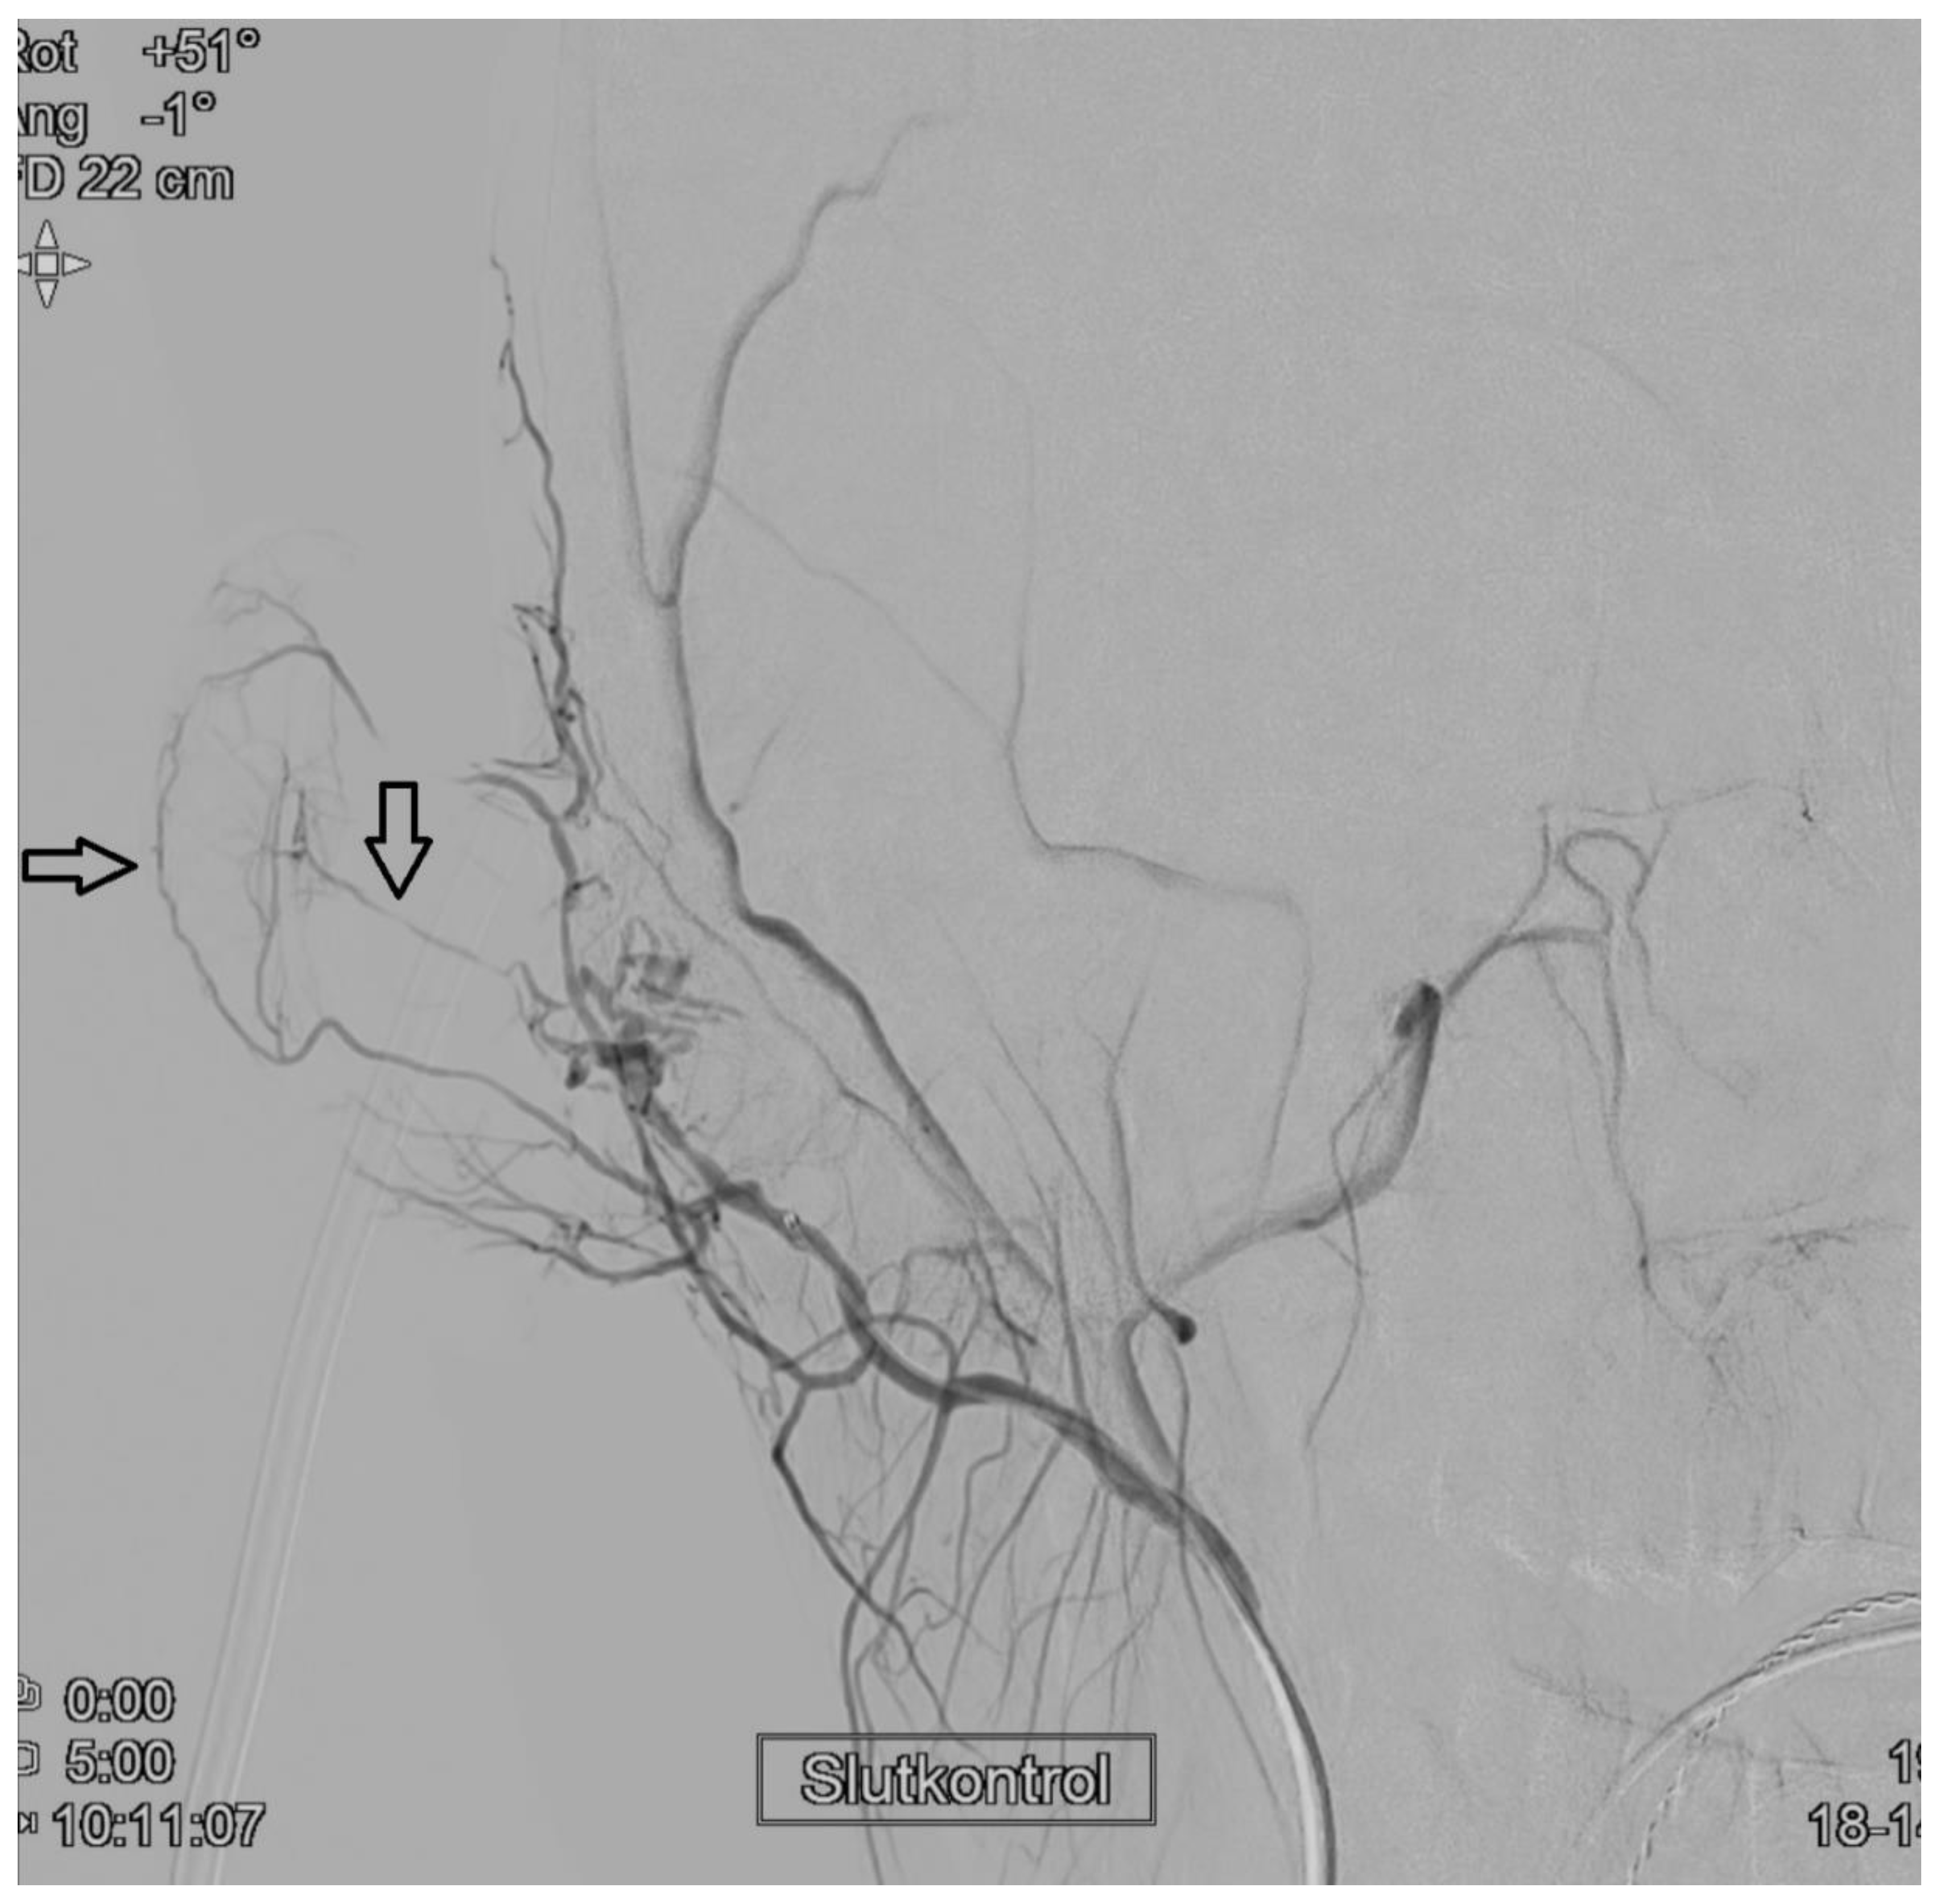

2. Case Report